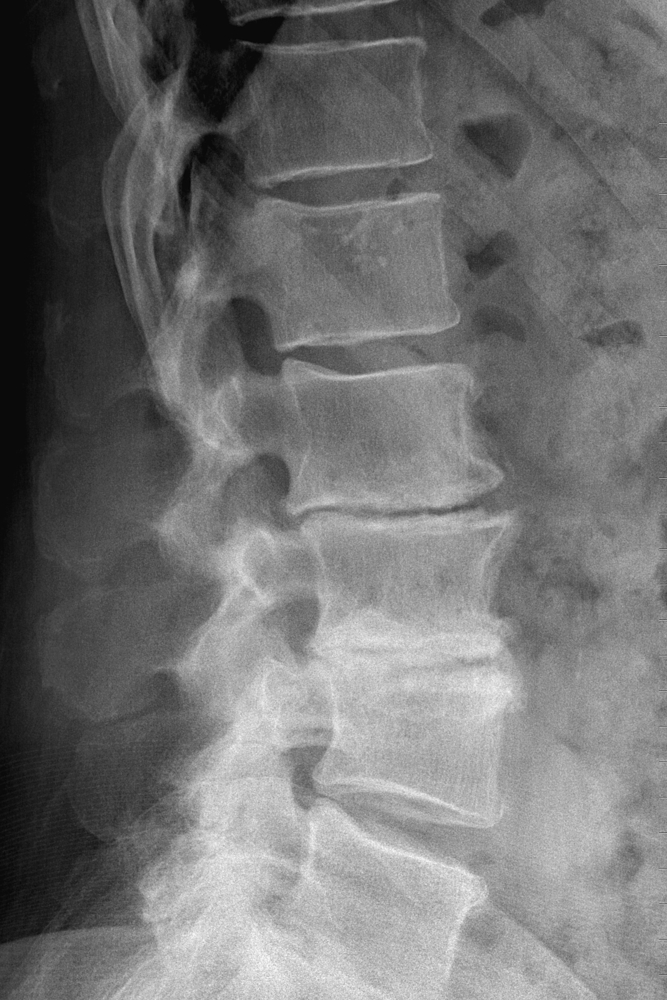

xray showing degenerative disc disease at lumbar vertebrae L56, lateral view, 40 year old male Do Disc Problems Show Up On Xray Studies have shown that mri findings of mild or significant disc degeneration are found on scans of patients with severe pain and minimal or no pain. Narrowing of the disc spaces is due to reduced height of the intervertebral discs; The answer is not straightforward. Before deciding which type is best for your case, your doctor will first perform a. Do Disc Problems Show Up On Xray.

xray showing degenerative disc disease at lumbar vertebrae L56, medial view, 40 year old male Do Disc Problems Show Up On Xray The vertebral body endplate surfaces may become sclerotic (whiter than normal), thickened and irregular. The causes of chronic low back or leg discomfort can be many. Studies have shown that mri findings of mild or significant disc degeneration are found on scans of patients with severe pain and minimal or no pain. The answer is not straightforward. Medical tests doctors. Do Disc Problems Show Up On Xray.